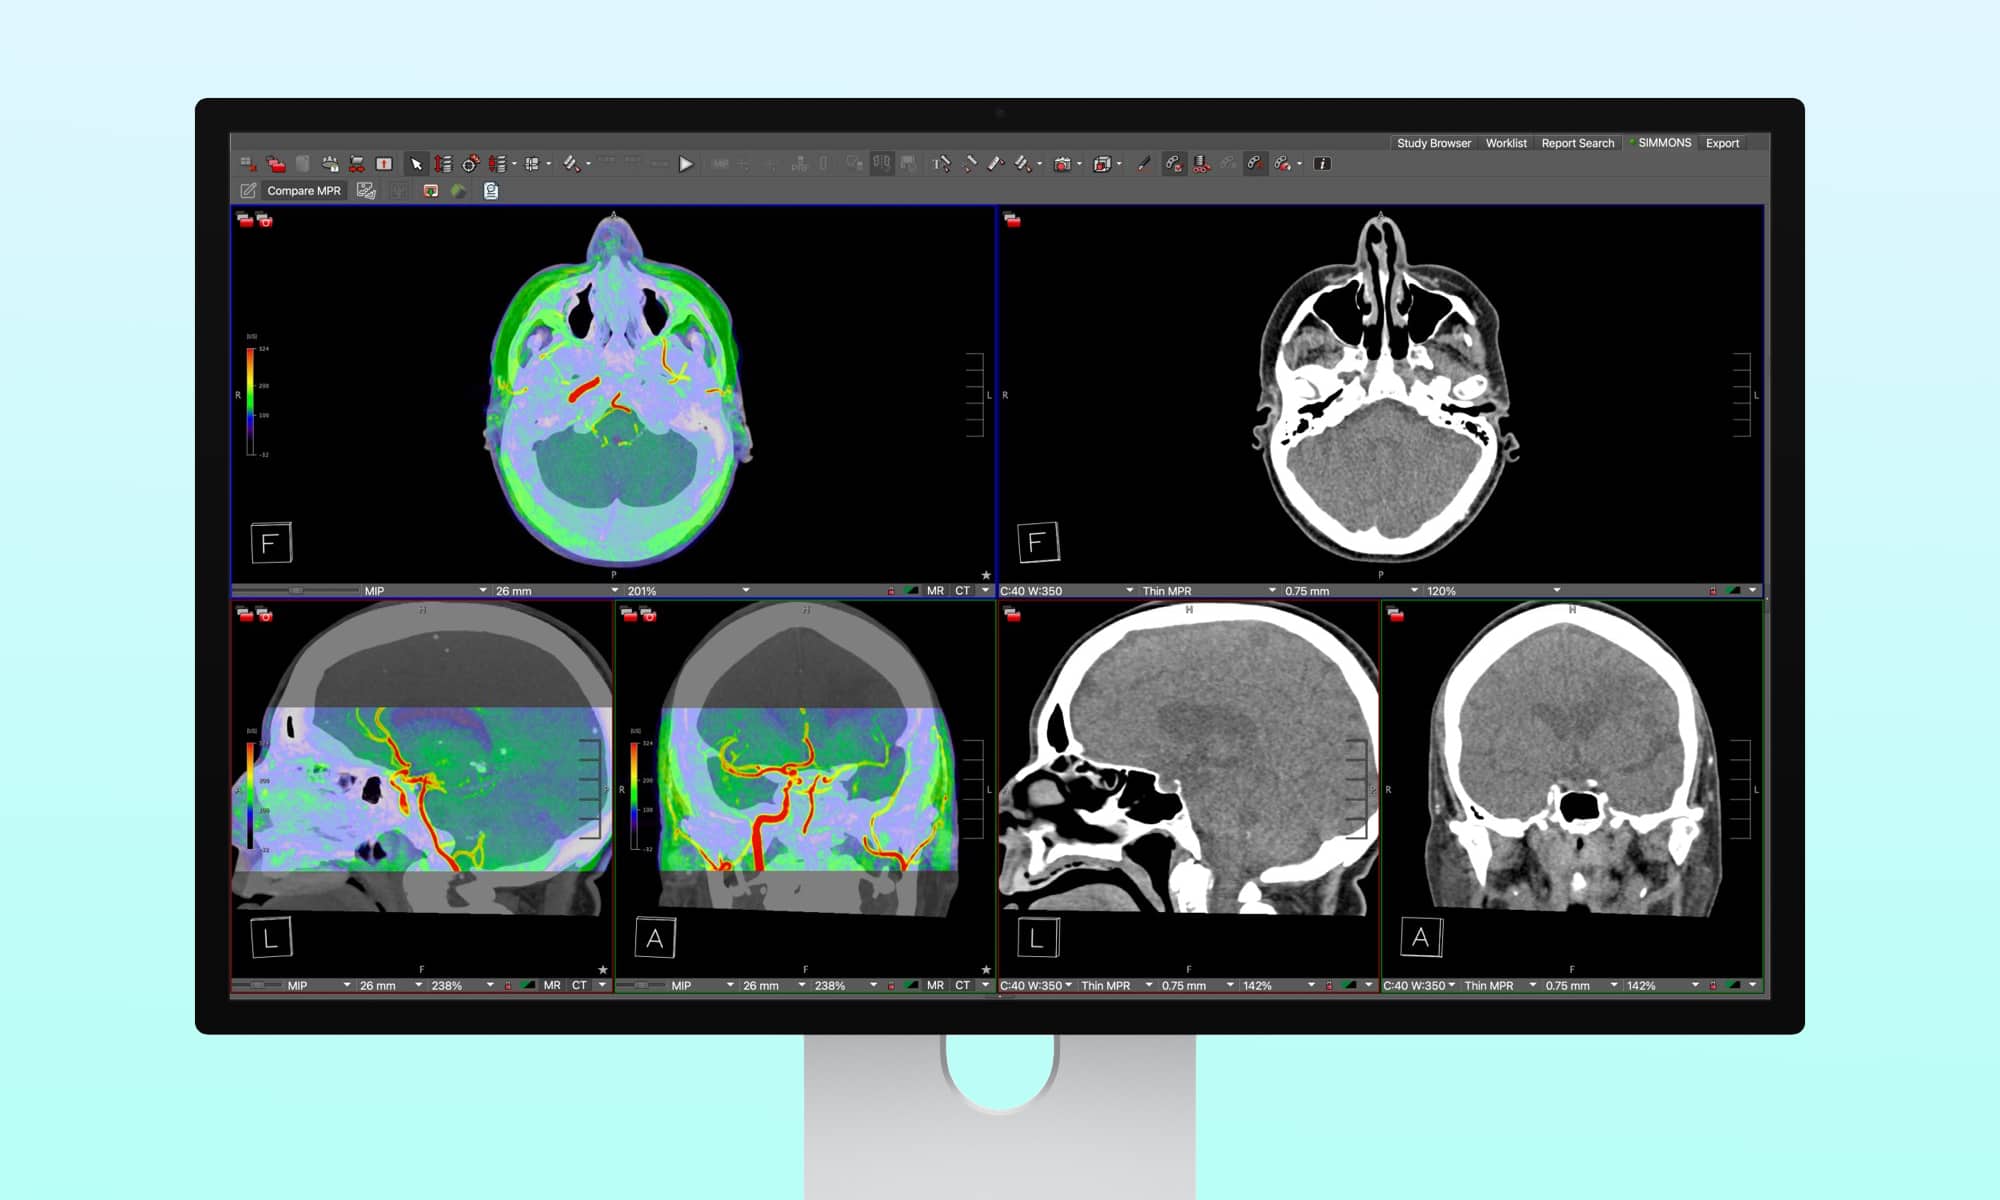

Apple’s latest Studio Display XDR has recently received approval from the US Food and Drug Administration (FDA) for use in diagnostic medical imaging, marking a significant milestone for the device. This development not only highlights the display’s suitability for professional photo and video editing tasks but also underscores its precision and reliability in critical healthcare applications.

The capability to support medical imaging is one of the 16 Reference Modes offered on the Apple Studio Display XDR. When the display was introduced in early March, Apple included “Medical Imaging (DICOM-350 nits)” and “Medical Imaging (DICOM-600 nits)” among the available modes. However, it was specified that these modes were intended for medical professionals and not for mammography.

The Studio Display XDR now supports medical imaging for diagnostic radiology, provided that the new medical imaging presets and Medical Imaging Calibrator within macOS are utilized. These features are designed for trained medical professionals in general radiology, excluding mammography. The display incorporates two distinct medical imaging reference modes to cater to the preferences of radiologists.

Obtaining FDA clearance for medical diagnostic use is crucial, with the focus primarily on the “Medical Imaging Calibration Feature (MICF).” The FDA granted approval on April 1, approximately four months after the feature was initially submitted on November 17, 2025, highlighting the extensive planning required by Apple for such functionalities.

Greg Joswiak, Apple’s Senior VP of Worldwide Product Marketing, confirmed the availability of the MIC tool in macOS 26.4, following the FDA clearance.

The Medical Imaging Calibration feature for Studio Display XDR has received FDA clearance and is now accessible on macOS 26.4 in the US! This enables radiologists to utilize the world’s premier professional display in general radiology. The convergence of health and technology is truly remarkable. ? pic.twitter.com/vXDIFLnHeW— Greg Joswiak (@gregjoz) April 7, 2026

Although the starting price of $2,899 for the VESA mount adapter version or $3,299 for the stand-equipped version may seem steep, it is reasonable for professionals in creative or medical fields. Comparable high-end 12MP diagnostic displays can exceed $30,000 in cost, despite having lower resolution than Apple’s 5K display. Each type of display excels in different aspects, with diagnostic displays handling tasks such as mammography that Apple’s display cannot.